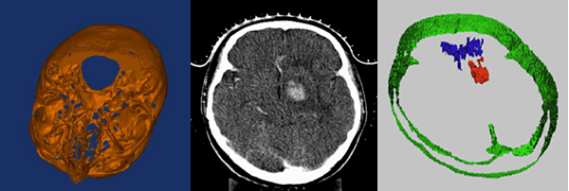

4、三维图像重建及分析

三维重建是指对三维物体建立适合计算机表示和处理的数学模型,是在计算机环境下对其进行处理、操作和分析其性质的基础,也是在计算机中建立表达客观世界的虚拟现实的关键技术。